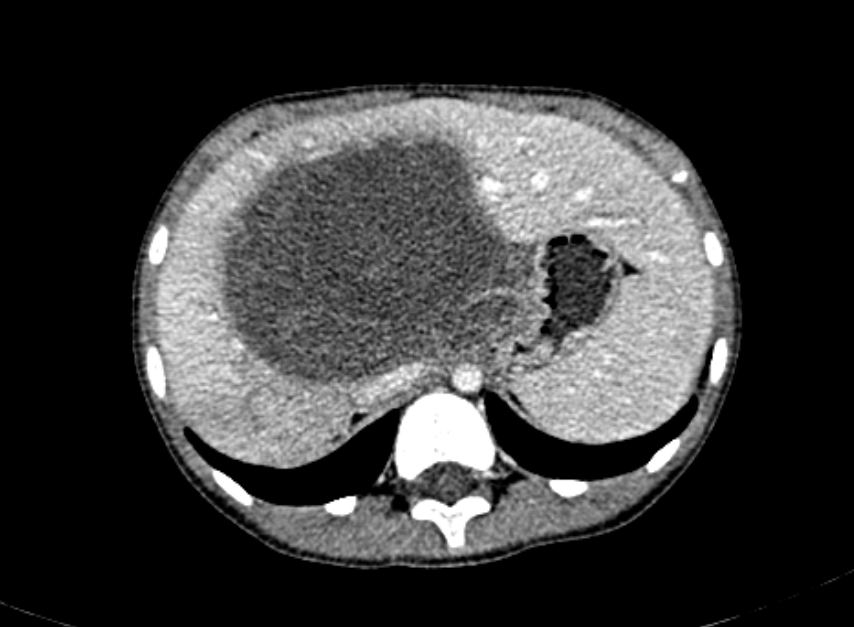

1、CT检查 表现多种形态,通常为单或多发的低密度灶,CT值15~45HU,以多个结节最常见。分布于肝的外围部为主。增强时轮廓更鲜明。等密度的转移瘤增强前后对比观察尤为重要。部分肿瘤由不同密度区为肿瘤坏死,周边常有环行增强。偶见薄壁囊样或较高密度的转移瘤。部分转移瘤影象学征象与原发瘤所见相同。见图12。

图12:示肝脏内恶性淋巴瘤转移的CT所见,男,6岁

2、MRI检查 用于评价肝内病变有助于鉴别良恶性肿瘤。在各种影象学检查中,MRI发现肝转移瘤最敏感。因此,MRI可作为一种重要的检查方法。多数转移瘤T1、T2延长,在T1加权像上为低信号,T2加权像上为高信号。转移瘤的形态不规则,边缘不清,大小不等。由于瘤体内可出现坏死、囊变、出血、脂肪浸润、萎缩、纤维化、钙化等改变,MRI信号可不均匀呈混杂信号。此外,在T2加权象上肝转移瘤可出现“靶征”或“牛眼征”,表现为信号高低不一的晕环。

不同恶性肿瘤的肝内转移,其影像学改变也不尽相同。神经母细胞瘤转移灶可呈多种形态:①散在低密度结节含钙化;②多个结节互相融合,呈一个巨块型分叶状密度不均等的肿块,类似肝内原发瘤。此时需十分注意肾上腺区有无肿块或腹膜后淋巴结转移;③肝脏普遍性增大,密度稍减而不均匀,示细小结节分布;④正常肝形态。